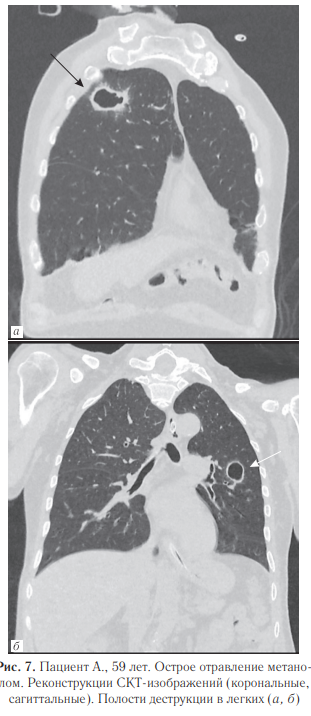

При проведении судебно-медицинской экспертизы выявлены массивные билатеральные гематомы головного мозга (данные аутопсии представлены на рис. 3), а также инфильтративные изменения в легких с полостями абсцессов (рис.10). Исследования легких: при поступлении (рис. 4), рентгенограмма органов грудной полости (рис. 5) и СКТ груди с реконструкциями в динамике через 1 месяц (рис. 6–8).

На рис. 9 представлена рентгенограмма органов грудной полости, выполненная перед смертью пациента. Гистологическая картина по данному случаю отравления. Головной мозг: кровоизлияния (гематомы) с организацией, глиальным рубцом по периферии, с лейкоцитарно-ядерным детритом, слоистым фибрином на фоне эритроцитарных масс; тромбоз некоторых сосудов, кое-где с перифокальным воспалением; фибриноидный некроз стенок отдельных сосудов. Отек головного мозга, местами вплоть до сетчатости, с очагами нейронодистрофии, фокусами выпадения нейронов; прогрессирующий склероз, отек пиальных структур коры головного мозга. Глиальный рубец (в подкорковом отделе), с участками нейронодистрофии, с фокусами кариорексиса, кариолизиса к карнификации; очаговая инфаркт-пневмония (в одном из срезов) с гнойным воспалением, с очагами абсцедирования, местами с признаками организации; полнокровие сосудов с эритро-, лейкостазами, тромбами с фибрином в просветах некоторых сосудов в легких. В сердце: неравномерно-концентрический фиброгиалиноз стенок артериальных сосудов с умеренным сужением просветов отдельных сосудов; периваскулярный, очаговый межуточный сетчатый фиброз; фокусы липоматоза в строме; хаотичное расположение, полиморфизм кардиомиоцитов; фокусы миофрагментации, волнообразной деформации мышечных волокон; неравномерное кровенаполнение сосудов с участками венозно-капиллярной гиперемии.